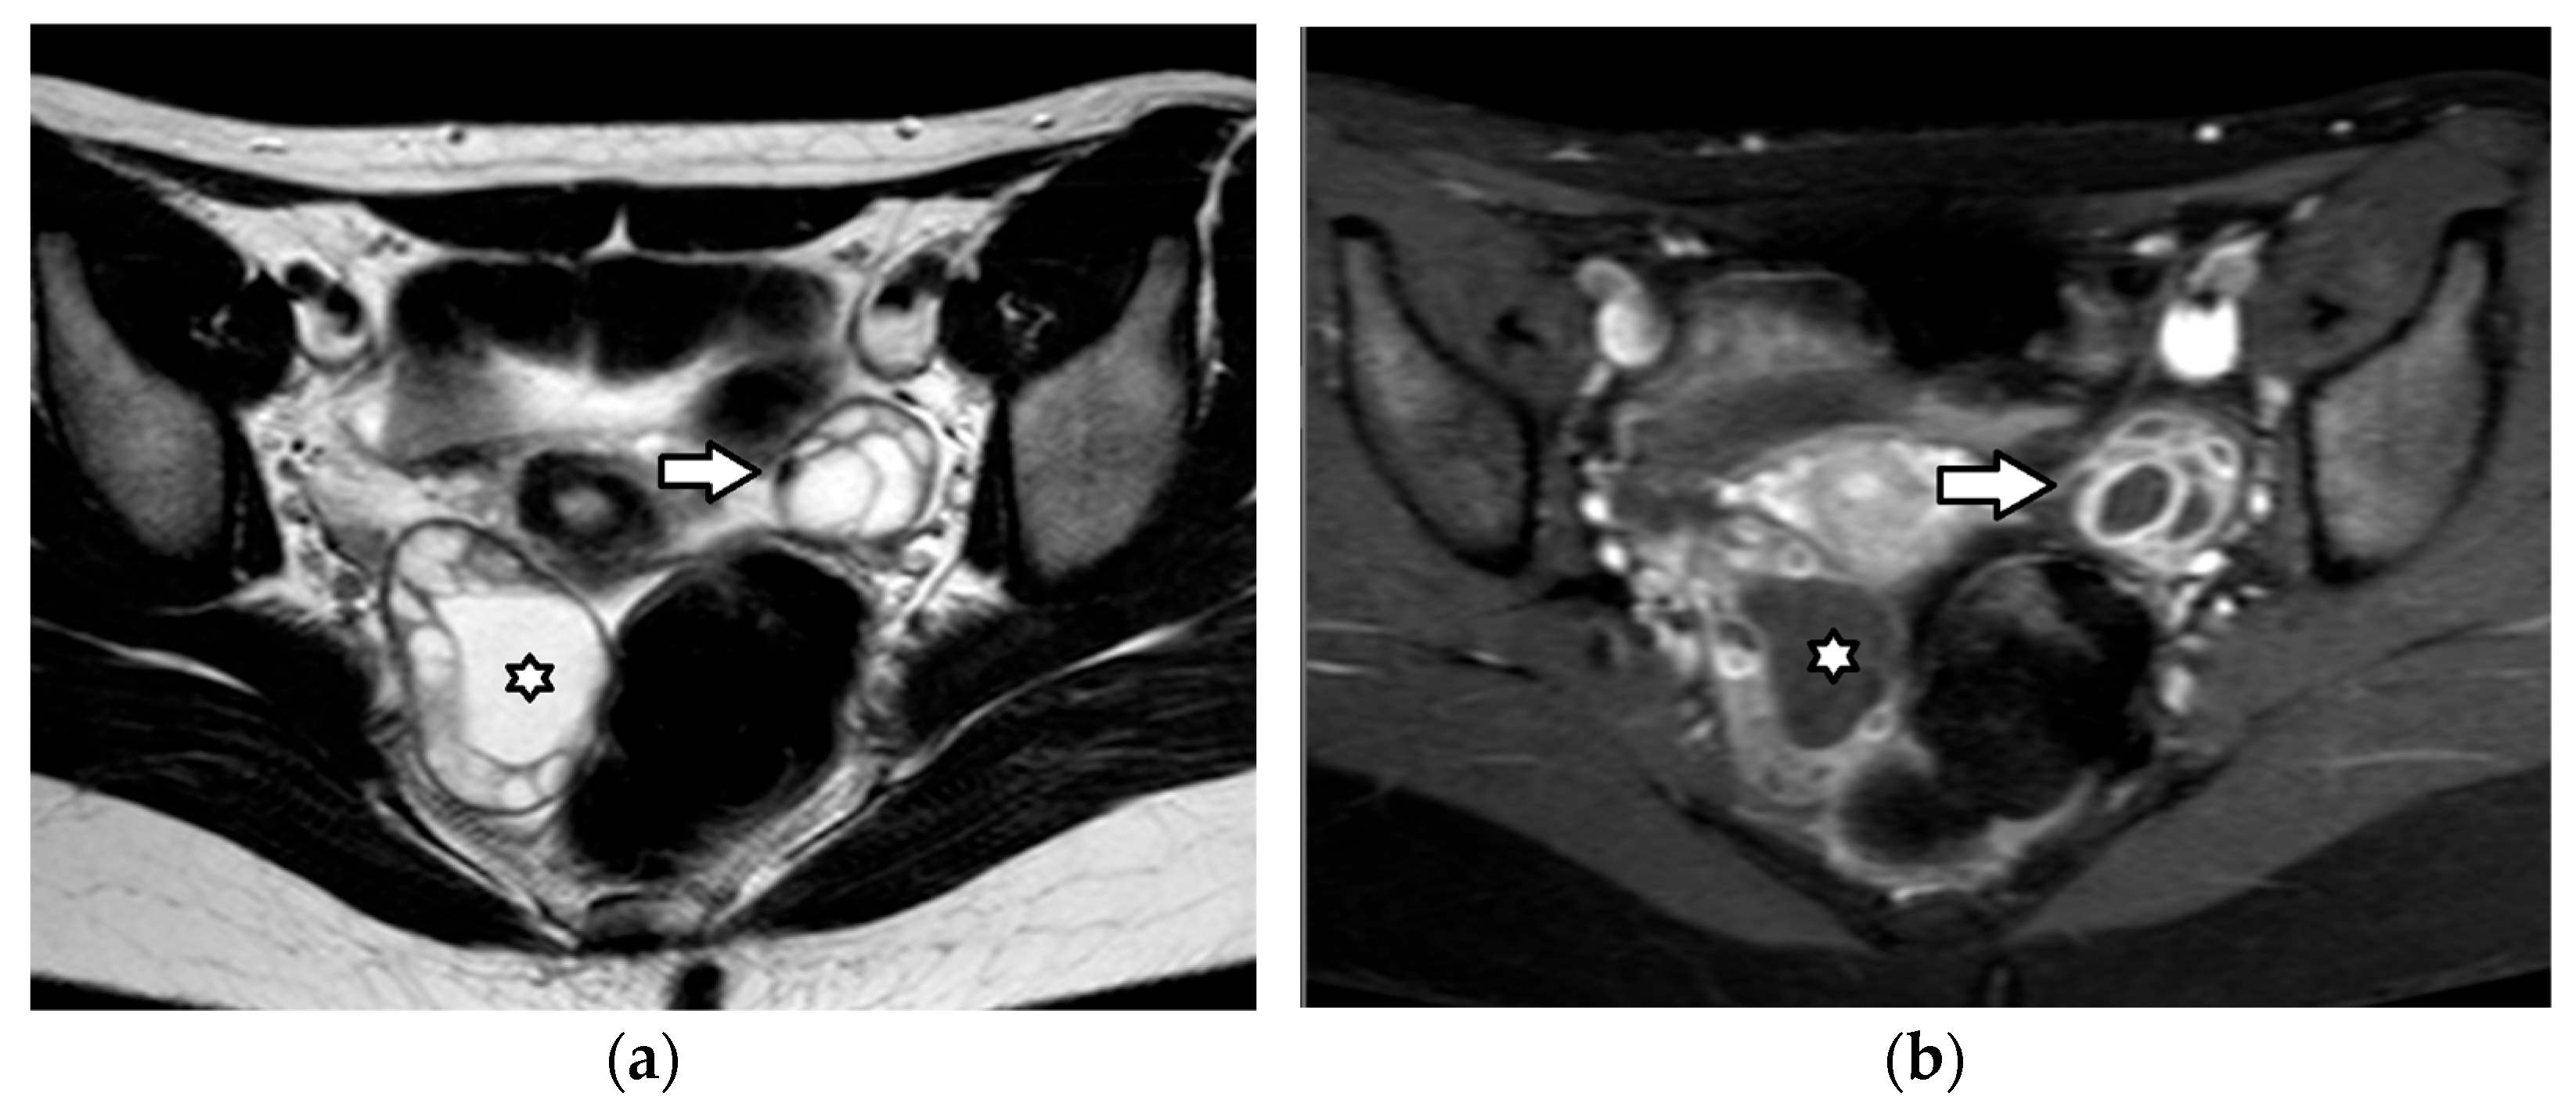

| Juvenile granulosa cell tumor | 75% of SCSTs mean age: 13 years bilateral: 4–5% secretes estrogens: signs of isosexual peripheral precocious puberty or menstrual irregularities secretes androgens: virilization (rarely) possible association with enchondromatosis syndromes: Maffuci syndrome, Ollier disease | malignant often diagnosed at an early stage excellent prognosis recurrence: rare | estrogens androgens (rarely) inhibin, especially inhibin B Müllerian Inhibiting Substance | nonspecific large size (mean diameter, 12.5 cm) multicystic tumor, with solid vascular components MRI

|